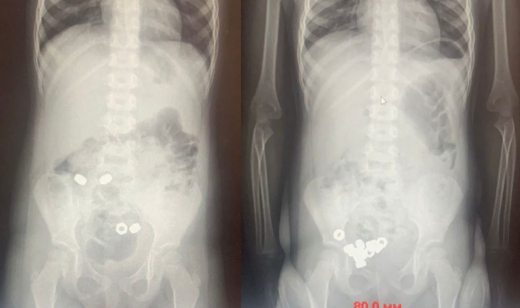

Почти два десятка гаек проглотил трёхлетний воронежец. Извлечь их удалось, не проводя малышу операцию. Маленькому пациенту оперативно пришли на помощь медики ОДКБ №2. Об этом сообщили в телеграм-канале регионального Минздрава в понедельник, 17 ноября.  Когда малыш поступил в приёмное отделение, его родители сразу заявили, что он мог проглотить инородные тела. Впрочем, какие-либо симптомы этого не проявились. Тем не менее подозрения взрослых оказались небеспочвенны.  Врачи провели рентген брюшной полости. Тот показал наличие 16 маленьких гаек в желудочно-кишечном тракте ребёнка. Его пришлось госпитализировать для динамического наблюдения: слишком высок был риск развития осложнений. Поскольку малыш проглотил всё-таки не магниты, медики выбрали консервативную тактику решения его проблемы. Ребёнку назначили диету, покой, контроль стула и рентгенографию в динамике. Этого, надо сказать, оказалось достаточно. К третьему дню все гайки вышли естественным путём. Затем ребёнка выписали из больницы. Кстати, минувшим летом двухлетний мальчик из Воронежа проглотил десятки магнитов и попал на операционный стол. Три магнита буквально склеили стенки его желудка с кишечником. Спасали ребёнка также в Воронежской областной детской больнице №2.